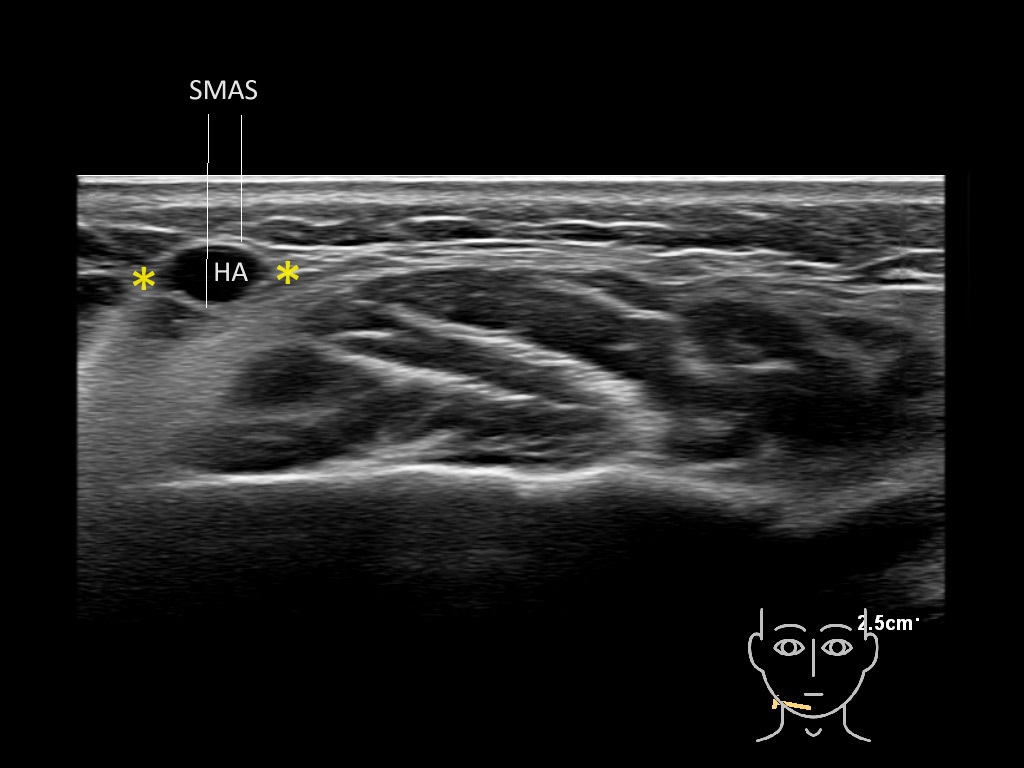

Filler deposits may end up unintentionally in the SMAS or fascial layers of the skin. Very often this will not lead to adverse events, however, adverse events ( nodules, migration / redistribution impaired muscle movement and smiling and malar edema) are are often related to filler ending up in the SMAS or fascia.

Study the first image to recognize the different layers. If you are sure about the layers, swipe to the second image to view the answer (if applicable).